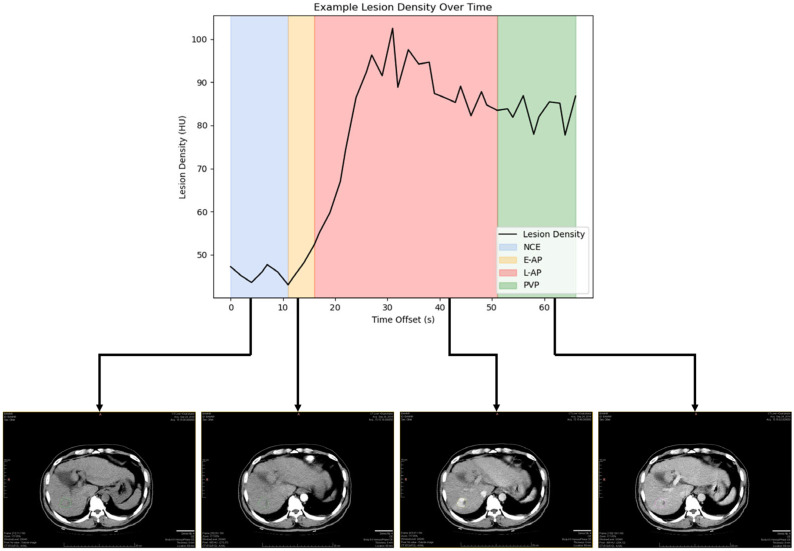

Methods: In this study, we investigated the variability of maximal lesion diameter and mean lesion density of HCC lesions on CT scans across four different contrast enhancement phases: non-contrast-enhanced phase (NCE), early arterial phase (E-AP), late arterial phase (L-AP), and portal venous phase (PVP). HCC lesions were independently segmented by two expert radiologists. For each pair of a lesion's scan timepoints, one was selected randomly as the baseline measurement and the other as the repeat measurement. Both absolute and relative differences in measurements were calculated, as were the coefficients of variance (CVs). Analysis was further stratified by both contrast enhancement phase and lesion diameter.

Results: Lesion diameter was found to have a CV of 5.11% (95% CI: 4.20-6.01%). About a fifth of the measurement's relative changes were greater than 10%. Although there was no significant difference in diameter measurements across different phases, there was a significant negative correlation (R = -0.303, p-value = 0.030) between lesion diameter and percent difference in diameter measurement. Lesion density measurements varied significantly across all phases, with the greatest relative difference of 47% in the late arterial phase and a CV of 22.84% (21.48-24.20%). The overall CV for lesion density measurements was 26.19% (24.66-27.72%).

Conclusions: Changes in tumor diameter measurements within 10% may simply be due to variability, and lesion density is highly sensitive to contrast timing. This highlights the importance of paying attention to these two variables when evaluating tumor response in both clinical trials and practice.